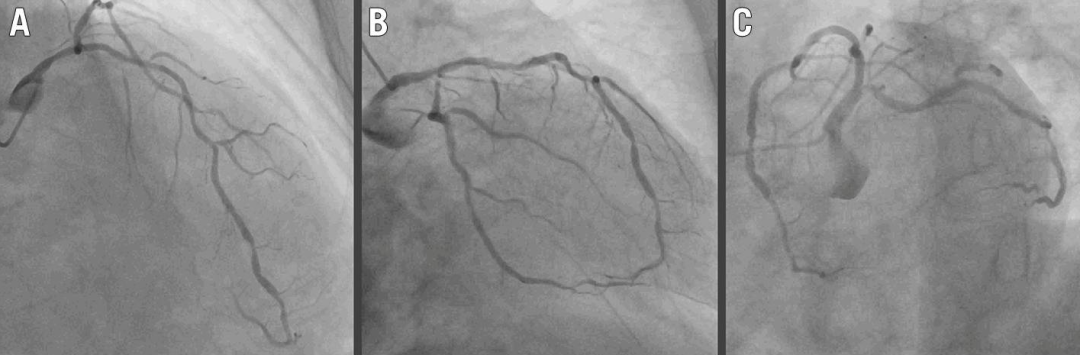

冠脉造影(图1A-C):

▹LCX开口重度狭窄(>90%)

▹左主干-LAD全程轻度狭窄(30-40%)

紧急冠脉造影(图1D-E,视频1、视频2):

LAD血流下降至TIMI 2级

夹层范围:LAD开口延伸至LAD近段

图 1. 术中冠状动脉造影、IVUS及随访造影

A-C. 初始冠脉造影:LCX开口重度狭窄,左主干-LAD轻度狭窄

D-E. 夹层发生:LAD夹层(虚线箭头),TIMI 2级血流,(D'、E')放大图像

H. 灌注球囊封堵入口:LAD血流恢复

I. 灌注球囊远端开窗:建立真-假腔交通

K-L. 灌注球囊术后:最终冠状动脉造影,残余假腔存在

M. 9个月随访冠脉造影:夹层愈合

左主干-LAD及LCX行药物球囊扩张后,冠状动脉造影显示结果良好,但残余假腔存在(图 1K、图 1L)

2个月复查冠脉造影:仍有残余假腔

9个月复查冠脉造影(图1M):管腔通畅,夹层完全愈合